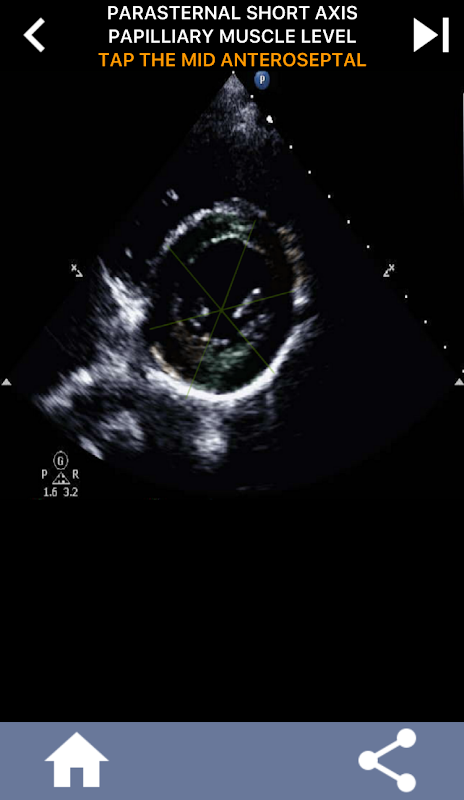

Quizbasierter visueller Ansatz zum Erlernen der AHA-Herzsegmente: Echokardiographie

Dieses Verständnis ist besonders wichtig, wenn der Kardiologe den genauen Ort eines Problems ermitteln möchte oder wenn der Bereitschaftsarzt ein Problem in einer bestimmten Region identifiziert und den Sonographen dazu veranlasst, das entsprechende Segment, beispielsweise die mittlere und untere Wand, genau anzuzeigen. Ein umfassendes Verständnis der AHA-Herzsegmente ist daher eine wesentliche Fähigkeit.

Diese App testet Ihr Wissen anhand echter Echobilder, was meiner Meinung nach oft die beste Lehrmethode ist.